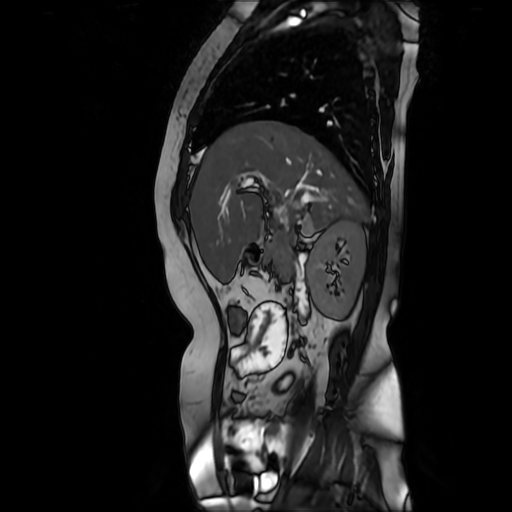

Paciente de sexo femenino, de 56 años de edad, refiere dolor en cuadrante superior derecho, indica que le realizaron colecistectomía de hace mas o menos 7 años, presenta cuadro de ictericia de 6 meses de evolución. Médico tratante le solicita estudio de Resonancia de vías biliares (Coilangioresonancia)

Se prepara a paciente previo a ingreso a zona 4 del área de resonancia magnética, paciente se presenta con catéter en región anterior del antebrazo, se utiliza bobina de abdomen de 16 canales y se procede a obtener localizadores en los tres planos, para luego adquirir imágenes en diferentes planos, en secuencias espin echo, eco de gradiente, secuencia de difusión. Se utiliza medio de contraste hepatoespecifico con dosis sugerida por fabricante.

HALLAZGOS IMAGENOLOGICOS

Se observa dilatación de las vías intra hepáticas a expensas de sus ramas hepáticas derecha, anterior y posterior, hepática izquierda y hepática común. El hepático común da la apariencia de estar anastomosado a un asa de intestino, lo que sugiere la posibilidad de una cirugía entero biliar.

No se logra observar el colédoco.